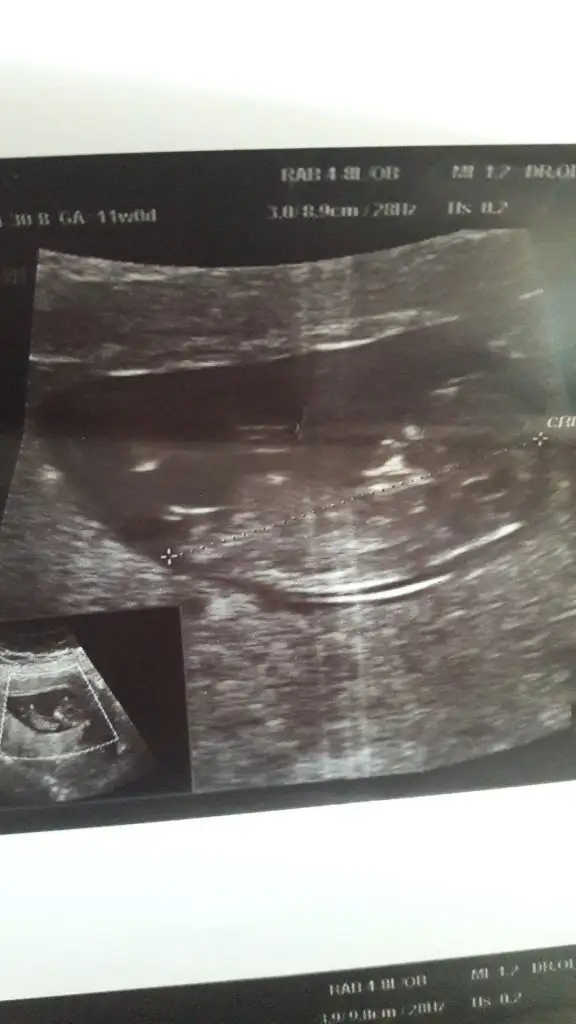

Yaa maşallah size yesinler sizi iki tane olunca da bi ayrı seviliyo bal lokmalarıKizlar banada cinsiyet yorumunda bulunur musunuz ? Ikiz benimkiler

erkek gibi geldiler maşallahKizlar banada cinsiyet yorumunda bulunur musunuz ? Ikiz benimkiler

Kizlar banada cinsiyet yorumunda bulunur musunuz ? Ikiz benimkiler

Yaa maşallah size yesinler sizi iki tane olunca da bi ayrı seviliyo bal lokmalarıIkra meyra daha iyi anlar ben tam anlayamadım

Doktorum birini kıza benzetti . Tabi önce sağlık ama gonlumuzde geçen bir kız bir erkekerkek gibi geldiler maşallah

Cinsiyet için bişey diyemeyeceğim hiç anlamam ama iki kese Allah’ım mucize ya maşallah

kafa yapılarından öyle geldi bana.doktorunuz daha iyii bilir tabikiDoktorum birini kıza benzetti . Tabi önce sağlık ama gonlumuzde geçen bir kız bir erkek

kafa yapılarından öyle geldi bana.doktorunuz daha iyii bilir tabikigönlünüzdeki sizin için hayırlısı olur inşallah sağlıcakla gelsinler :)